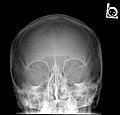

X-ray images and illustrations